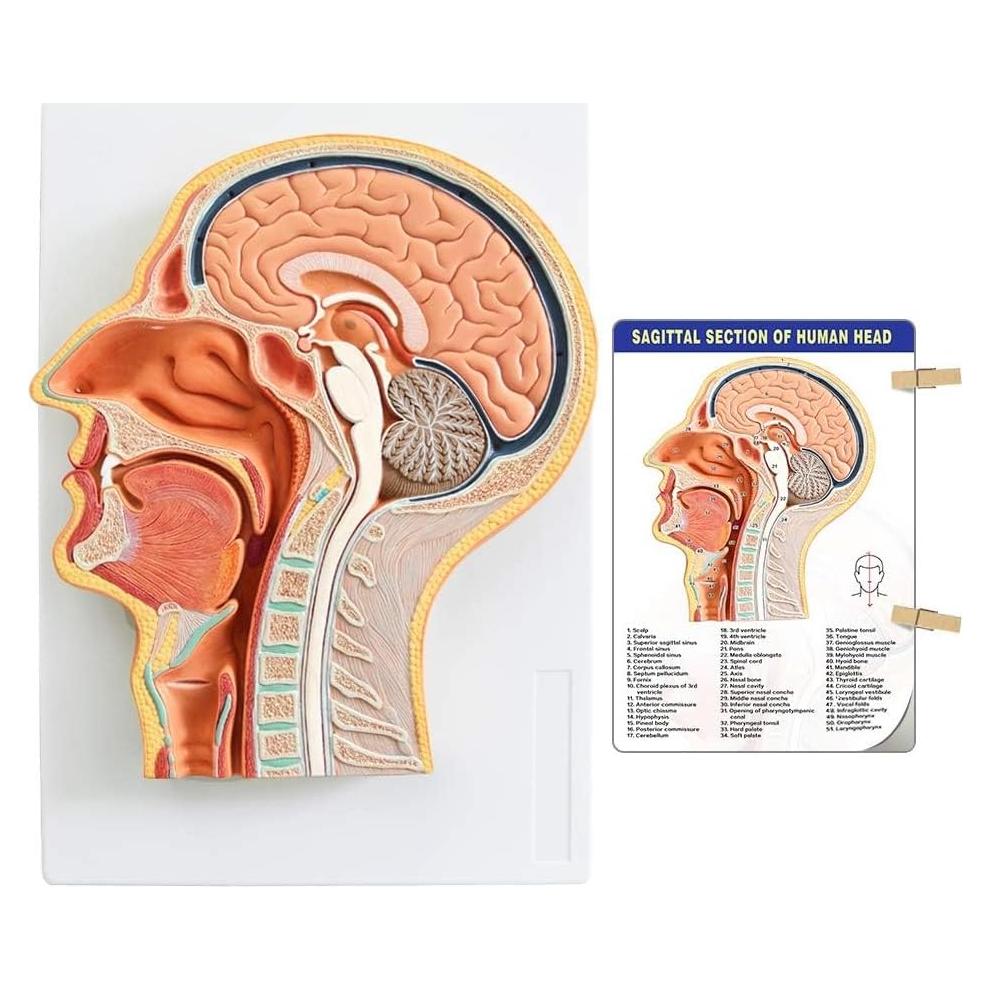

Modelos Anatómicos 3D EVOTECH SCIENTIFIC - Cuerpo, Corazón y Esqueleto